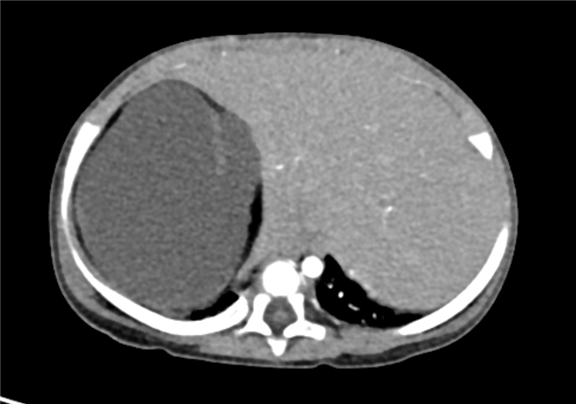

术前CT检查:

静脉期

上腹部增强CT:腹膜后巨大混杂密度肿块影,考虑畸胎瘤可能性较大